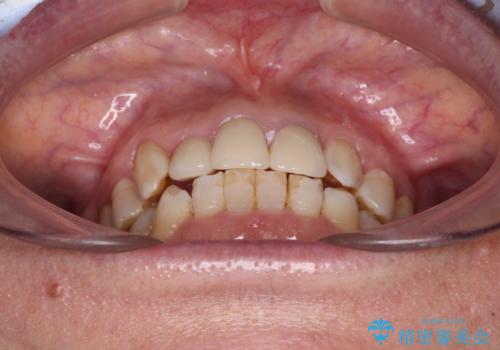

歯冠長延長術を行ったことで、自然な形態かつ清掃性の高いセラミッククラウンを装着することができました。

全顎的に治療を行ったため、治療期間も費用も負担は大きくなりましたが、統一感のある仕上がりとなりました。